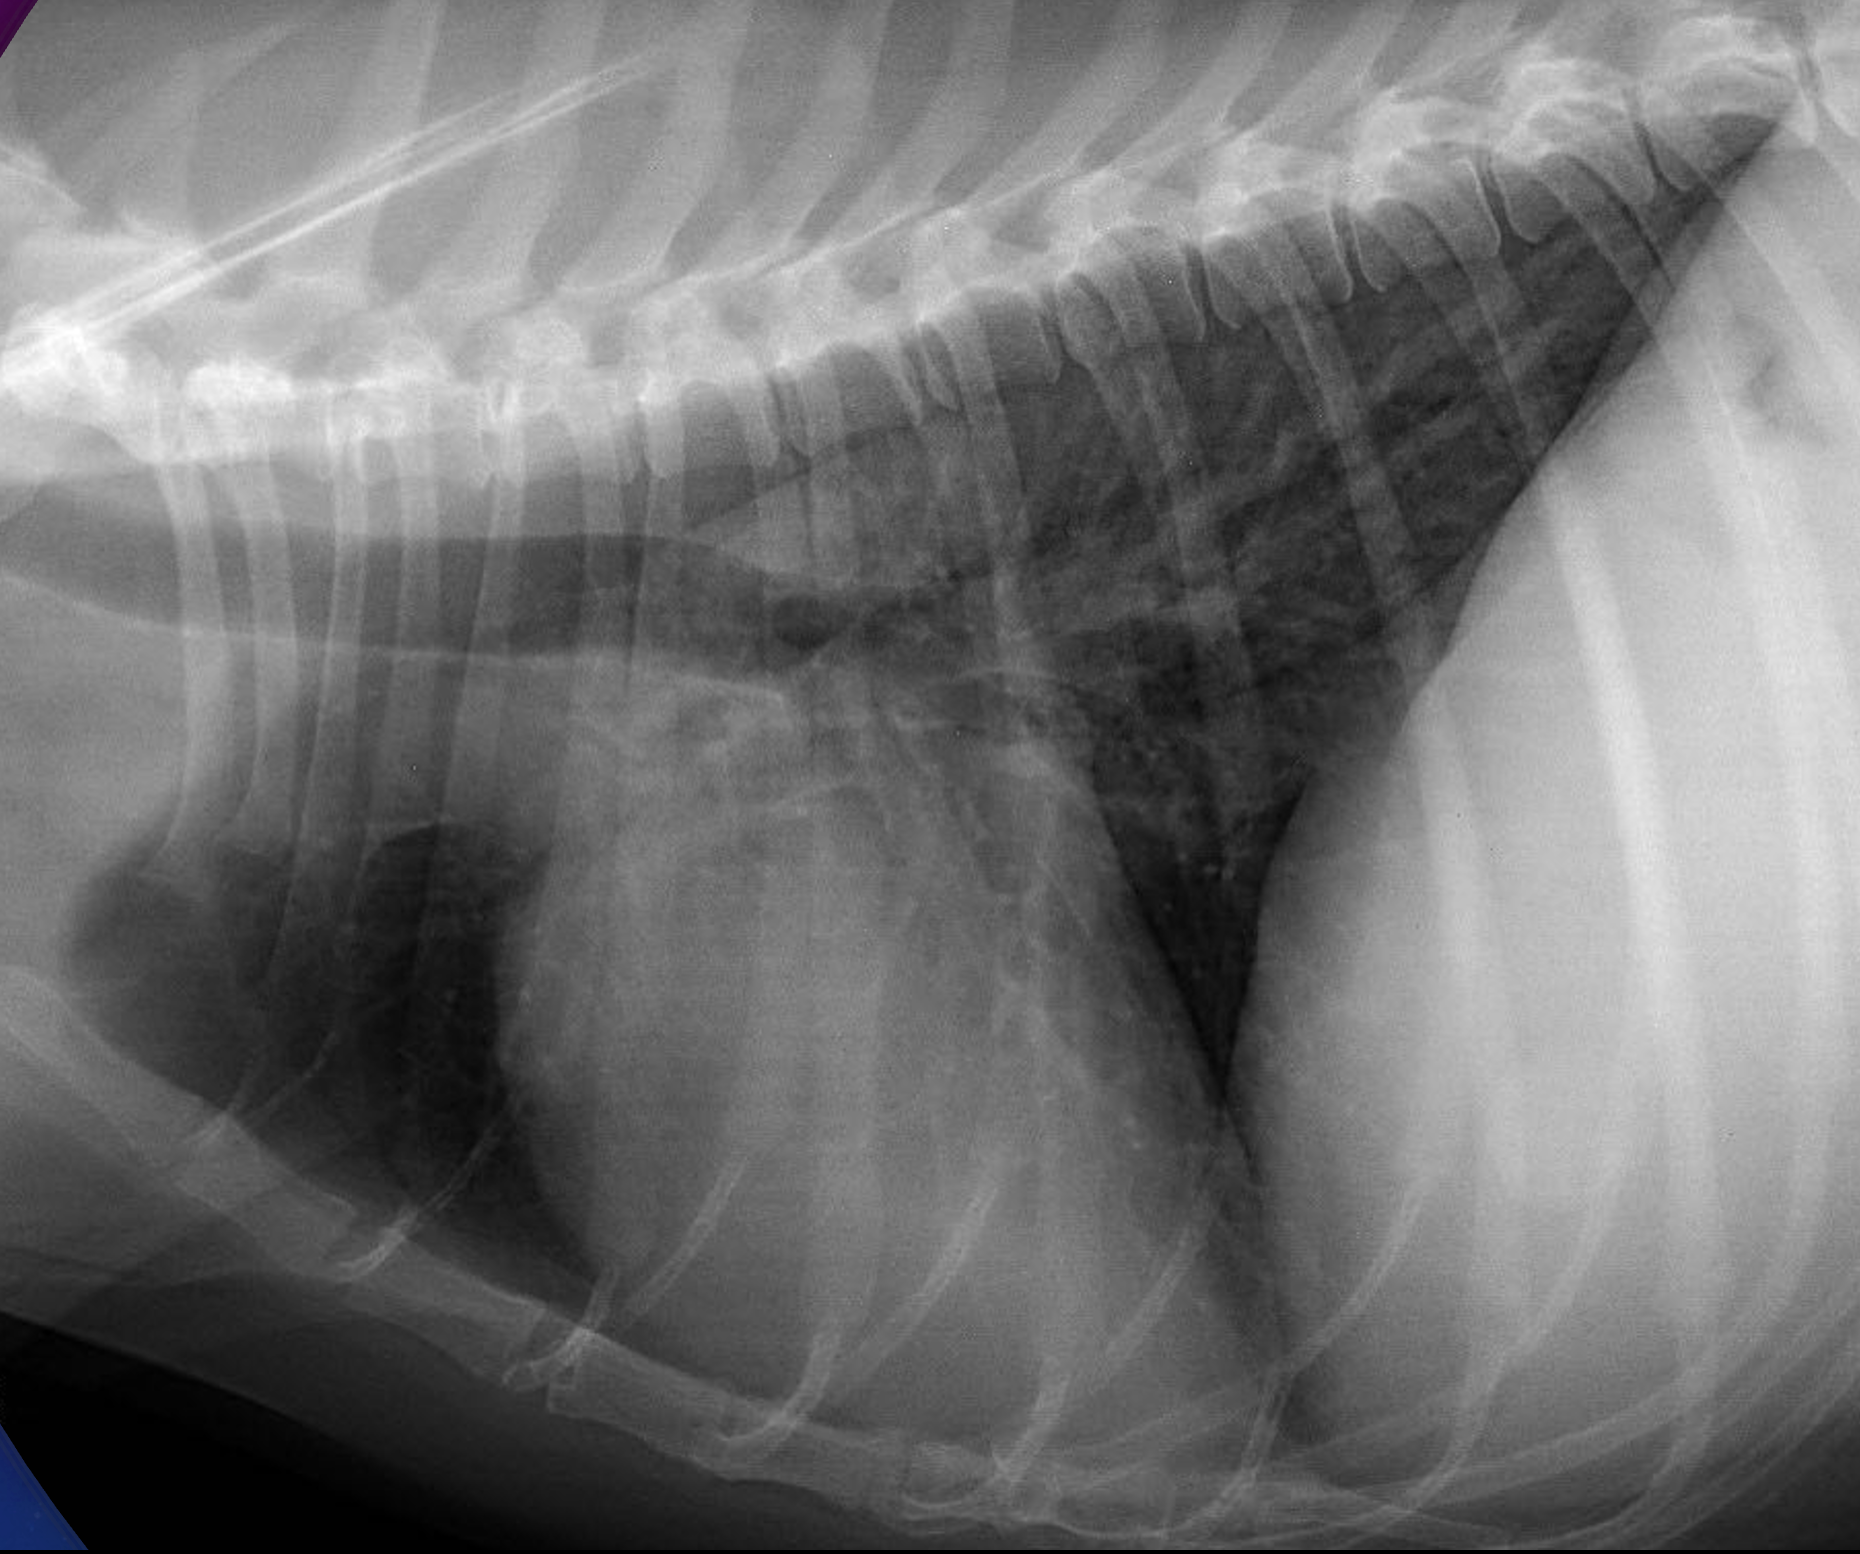

Hunder med hjertesvikt kan også få væskeansamling i buk, rundt lungene og rundt selve hjertet. Ved mistanke om hjertesvikt tar dyrlegen røntgenbilder av brysthulen, eller ultralyd av lungene, for å se etter lungeødem. Ultralydundersøkelse av hjertet utføres av veterinærkardiolog etter at vanndrivende medisiner har hatt god nok effekt til at hunden tåler å ligge på siden. Kardiologen legger en behandlingsplan og skriver ut resept på livsviktige medisiner.